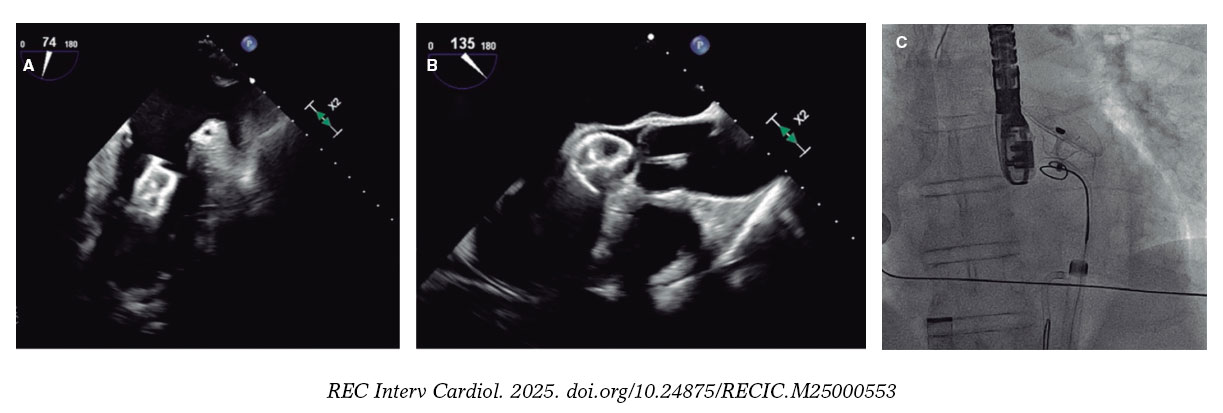

En la figura 5 y la figura 6 se muestran algunos ejemplos de embolización de dispositivos de cierre de la orejuela izquierda.

Figura 5. Ecocardiograma transesofágico (ETE) intraprocedimiento y fluoroscopia de cierre de la orejuela izquierda con un dispositivo Amulet de 25 mm. A: el dispositivo migró al ventrículo izquierdo (VI). B: se introdujo por un acceso femoral izquierdo un catéter guía JR4 de 8 Fr con un lazo de 20 mm que agarró el dispositivo por el tornillo del lóbulo distal y permitió traccionarlo a la aorta descendente. C: a continuación se canalizó la arteria femoral derecha con un introductor de 16 Fr, y con un catéter guía y un lazo de 30 mm se volvió a agarrar el dispositivo por el tornillo del lóbulo distal, que fue traccionado y finalmente extraído.